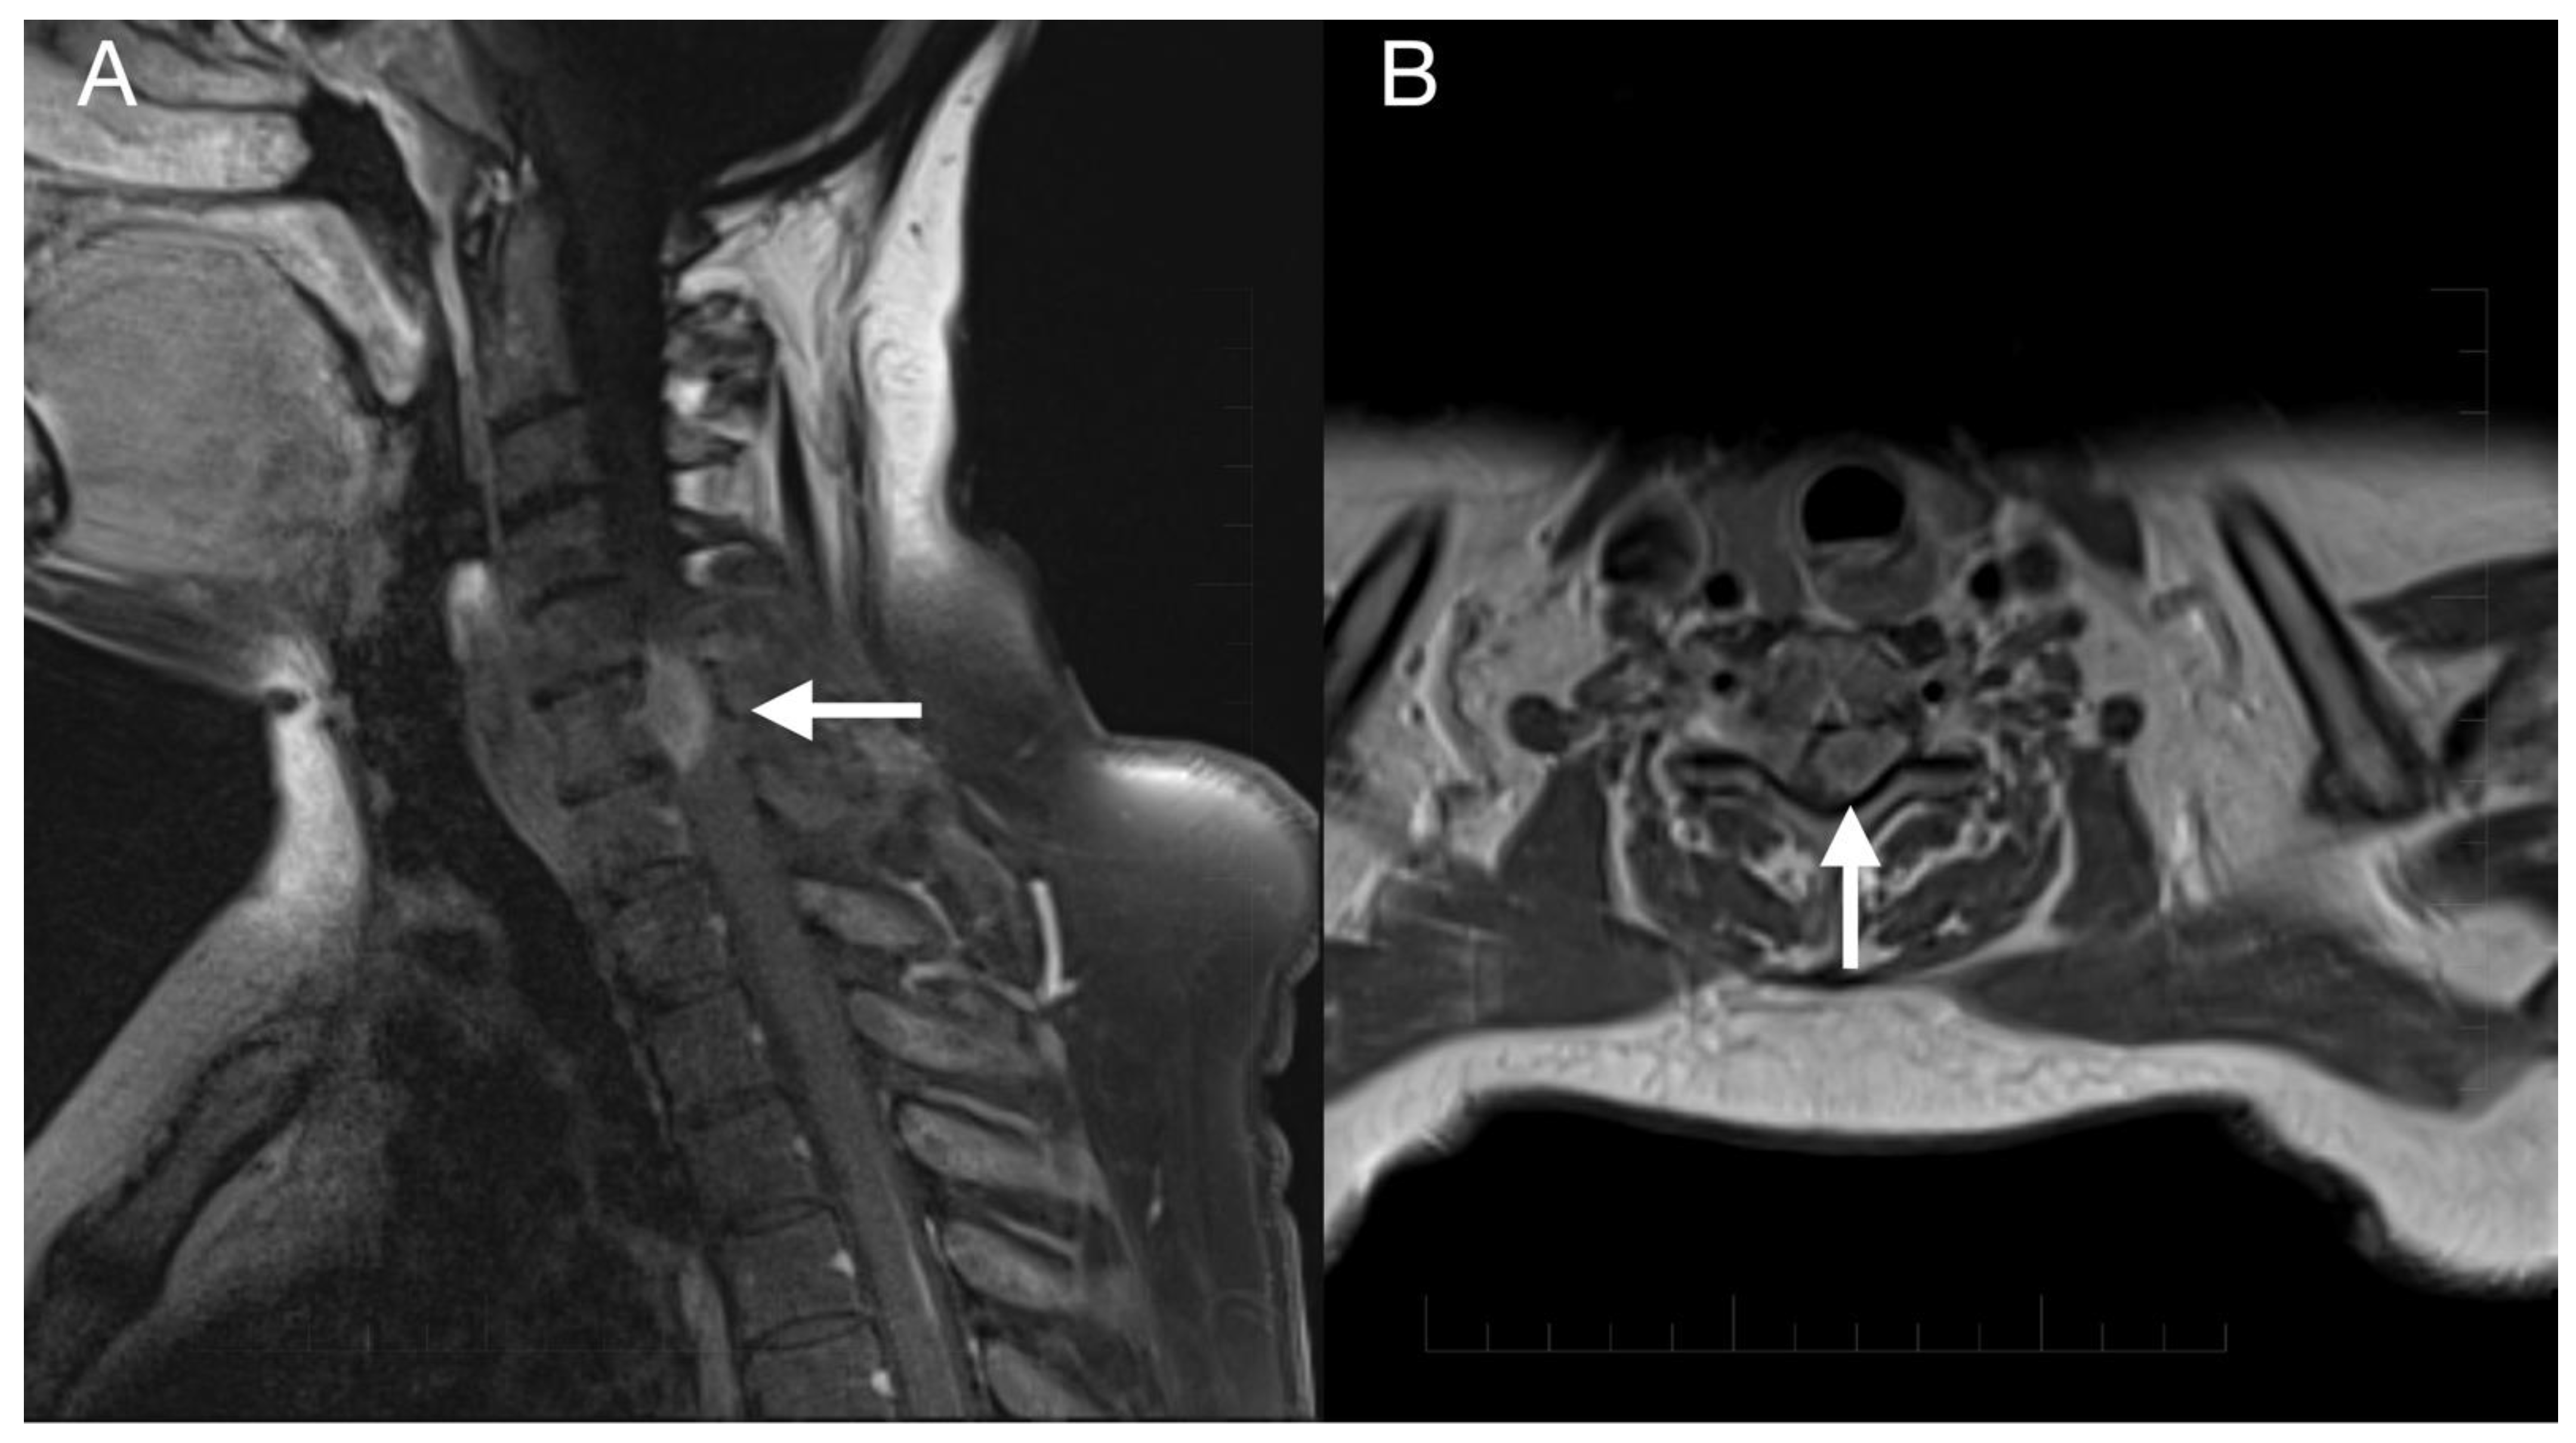

2. Case Report